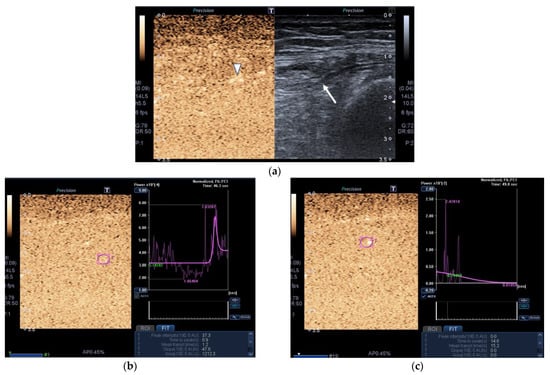

Figure 3.

Transversal QRF muscle of a matched healthy control (85 years old). (a) Transversal ultrasonography scan shows the QRF muscle (arrow) and vascularization after contrast-enhanced ultrasound (CEUS) administration (arrowhead). CEUS image and time–intensity curve analysis are shown using the built-in software. (b) ROI (pink circle) in the area of strongest enhancement indicates maximum perfusion in the QRF. (c) ROI (pink circle) in the area of lowest enhancement indicates minimum perfusion in the QRF.

Images of the peak maximum and minimum CEUS intensity of a patient and a healthy control are shown in Figure 3 and Figure 4.